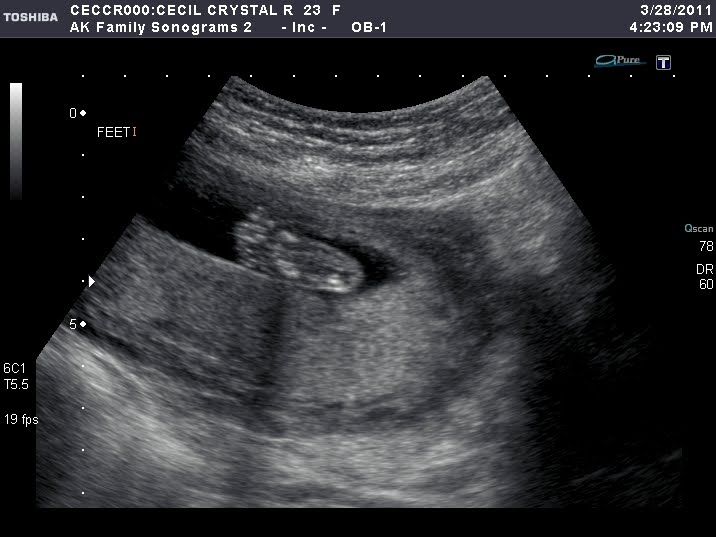

We are just three days away from the big ultrasound and our fingers are crossed that it will reveal whether we will be welcoming another baby boy or a baby girl into this world. As the days approach I find myself getting more nervous than ever before. My mind is continually playing out scenarios of our little family a year from now and I can’t stop envisioning what our lives are truly going to be like. Will our home continue to be filled with dinosaurs, trains, and robots, or is it suddenly going to be overrun with the color pink?!